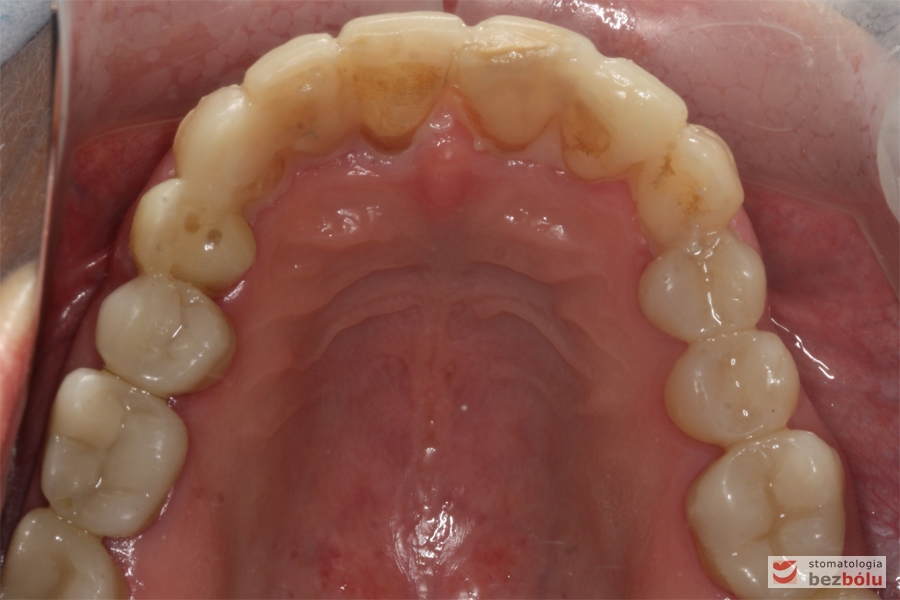

Szczęka - widok powierzchni okluzyjnej, stłoczenia i rotacje w odcinku przednim, zużyte wypełnienia w strefach bocznych

Szczęka – widok powierzchni okluzyjnej, stłoczenia i rotacje w odcinku przednim, zużyte wypełnienia w strefach bocznych